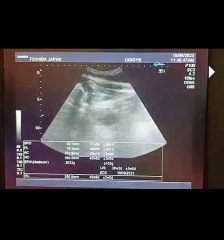

1 Male ♂️Gender at 37_38 Week with Difficult Sex Determination